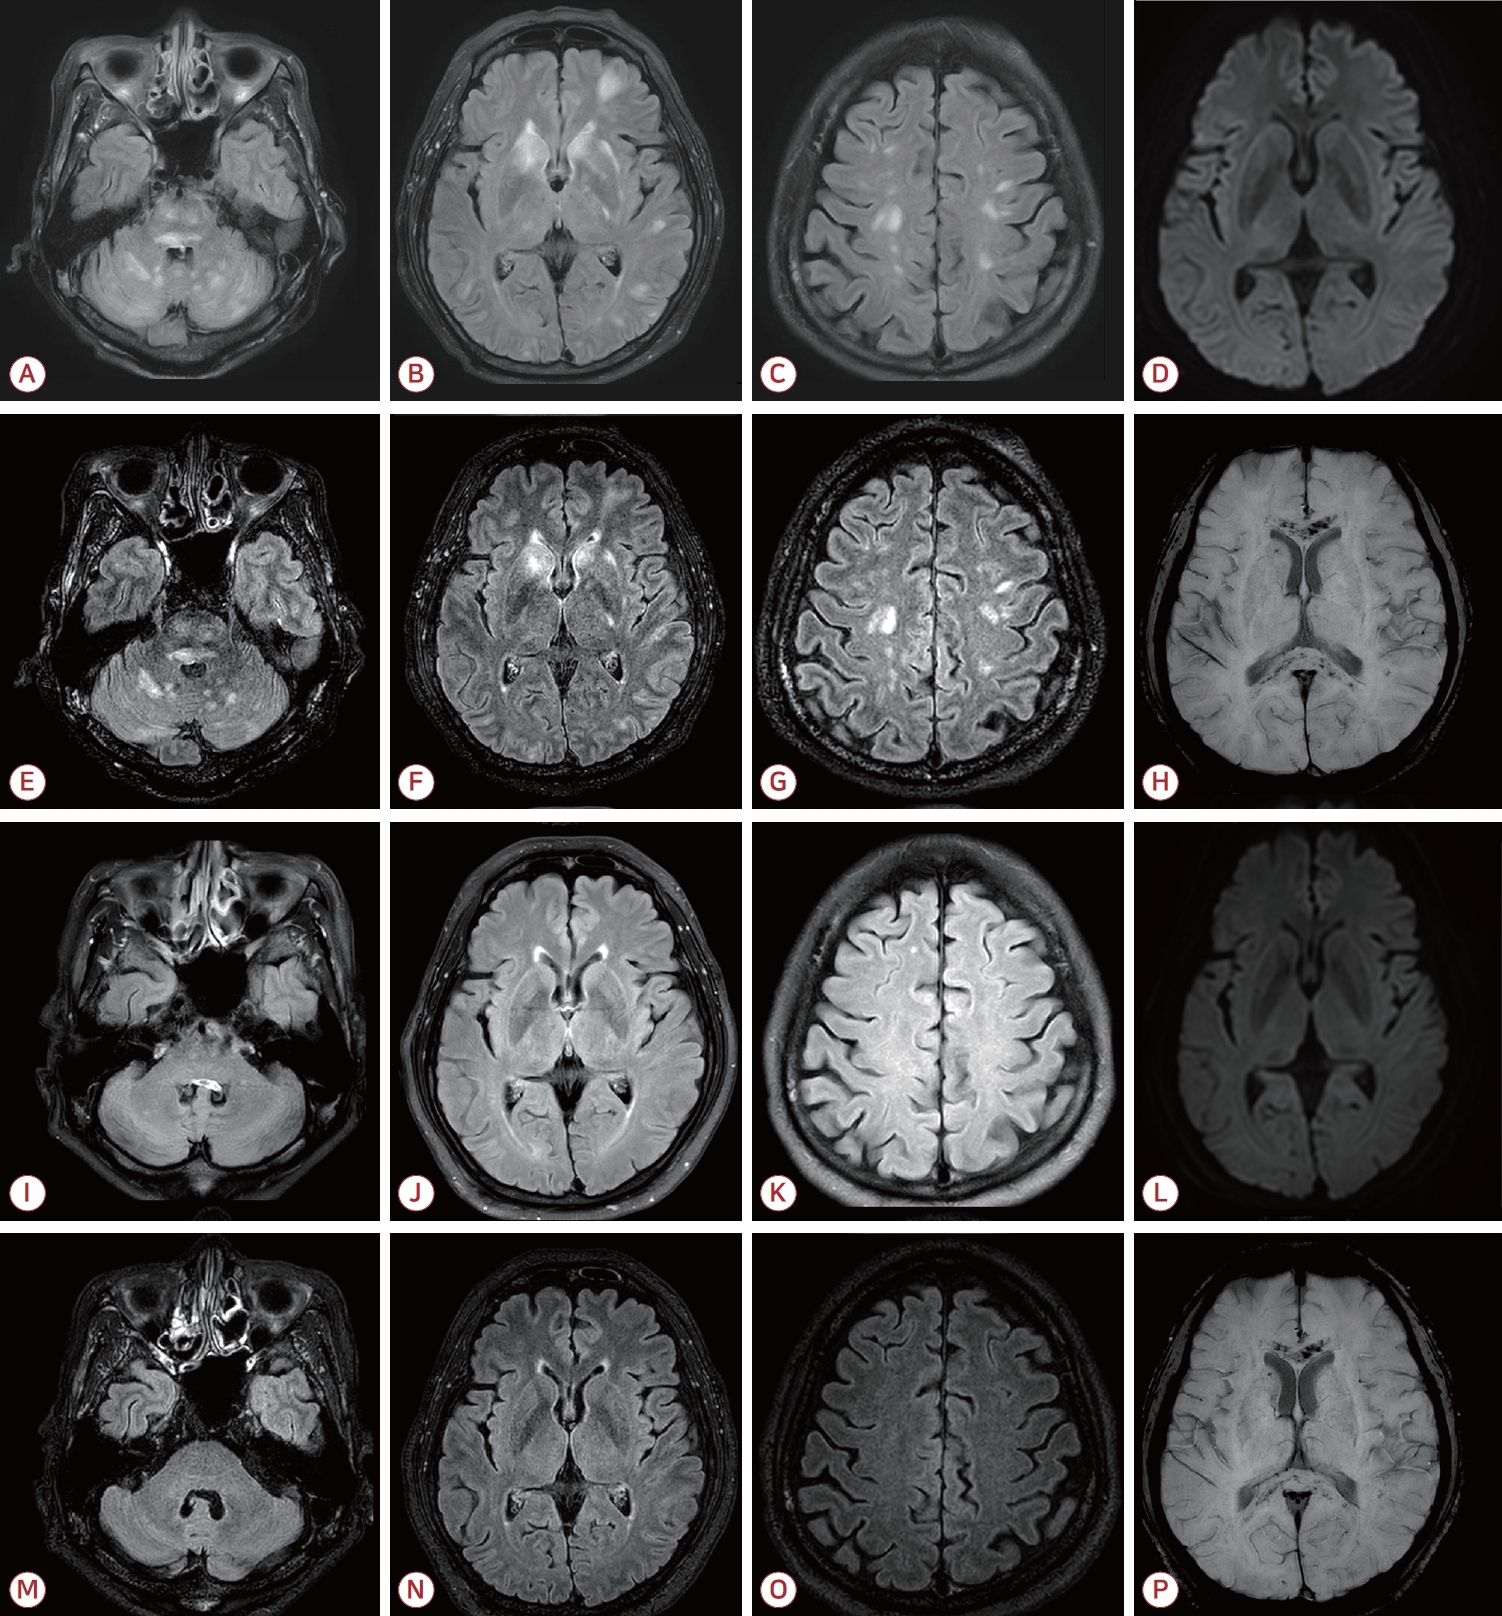

77세 남성이 하루 전부터 시작된 전신 쇠약감과 당일 발생한 의식 혼동을 주소로 응급실에 내원하였다. 환자는 5년 전 간세포암으로 우간 절제술을 받았으며 이후 우측 부신 전이가 확인되어 약 1년 전부터 3주 간격으로 총 17회에 걸쳐 아테졸리주맙과 베바시주맙 병합 요법을 받았고 마지막 투약은 내원 1개월 전이었다. 치료 기간 동안 특이 부작용은 없었으나 이후 추적 영상에서 하대정맥 침범을 동반한 재발과 다발 전이가 관찰되었다. 내원 당시 동공반사는 정상이었고 안구편위는 보이지 않았으며 근력은 정상이었다. 수막자극징후도 보이지 않았다. 혈압은 수축기 혈압이 170 mmHg 내외로 유지되었다. 말초혈액 검사에서 백혈구 3,700/mm3, 혈색소 10.4 g/dL, 혈소판 97,000/mm3로 경도의 범혈구감소증이 있었으며 혈중 암모니아는 135 μg/dL로 상승되어 있었다. 그 외 젖산, 소듐, C-반응단백 등은 정상 범위였고 뇌 computed tomography (CT)에서는 특이 소견이 없었다. 간성 혼수를 의심하여 관장 치료를 시행하였으나 의식 호전이 없어 뇌MRI를 시행하였다. MRI에서 뇌간, 소뇌, 심부회백질, 대뇌피질 및 피질하백질에 다발성 T2고신호강도 병변이 관찰되었고 조영증강액체감쇠역전회복(fluid attenuated inversion recovery, FLAIR)영상에서는 주로 뇌간과 소뇌, 일부 대뇌 반구에 작은 조영증강 결절이 확인되었다. 자화율강조영상(susceptibility weighted image, SWI)에서 뇌량과 양측 피질하백질에 광범위 미세출혈이 확인되었다(Fig. A-H). 뇌 전이 연관 탈수초질환이나 혈관염 가능성을 배제하기 위하여 뇌척수액 검사와 뇌파 검사를 시행하였으며 뇌척수액에서 세포 수 2/mm3, 단백질 92 mg/dL, 포도당 60 mg/dL로 경미한 단백 상승 소견이 있었고 세포 검사에서는 악성세포가 관찰되지 않았다. 항아쿠아포린-4항체, 자가면역항체 및 신생물딸림항체는 모두 음성이었다. 뇌파 검사에서는 전반적인 세타파 및 델타파가 관찰되었으나 뇌전증파는 없었다. 입원 4일째, 우측 반신마비와 발열(38℃)이 발생하여 경험적 항생제 치료를 시작하였다. 스테로이드 치료도 고려되었으나 다음날 의식 수준이 호전되었고 우측 마비도 완전히 회복되었다. 이후 재평가에서 경미한 구음장애가 있었으나 언어 기능은 거의 정상이었으며 입원 기간 동안의 사건전기억상실(retrograde amnesia)을 보였다. 추적 뇌파에서는 정상 배경파를 보였다. 환자는 재활 치료 후 신경계 후유증 없이 퇴원하였다. 퇴원 4개월 후 시행한 추적 MRI에서 대뇌, 뇌간, 소뇌의 다발성 고신호강도 병변은 거의 소실되었으나 광범위 미세출혈은 지속되었다(Fig. I-P).

기존 보고에 따르면 아테졸리주맙과 베바시주맙 병용 요법 이후 발생하는 뇌염은 대개 치료 초기 수개월 내 발병하며 면역억제 치료가 필요한 경우가 많다[3]. 그러나 본 환자는 치료 11개월째에 증상이 발생하였고 면역억제제 투여 없이 자발적으로 회복되었다는 점에서 전형적인 ICI 유발 뇌염과 차이를 보인다. 또한 가역 뇌병증과 함께 SWI에서 광범위한 미세출혈을 확인한 보고는 기존 ICI 유발 뇌염 관련 문헌에서는 확인되지 않았다.

따라서 본 증례에서 관찰된 미만성 미세출혈과 가역 뇌병증은 PD-L1 억제에 따른 별아교세포의 신경면역 조절 기능 저하와 베바시주맙에 의한 내피세포 기능장애가 복합적으로 작용하여 BBB 손상과 미세혈관 손상이 심화된 결과일 가능성이 있다. 아테졸리주맙과 베바시주맙은 각각 ICI 유발 뇌염과 BBB 및 내피세포 손상에 의한 가역후뇌병증(posterior reversible encephalopathy syndrome)을 일으킬 수 있는 약제이므로 두 약제를 병용하는 환자에서 뇌병증이 발생한 경우 두 가지 병태를 모두 감별하는 것이 중요하다. 특히 두 약제가 BBB 손상을 상호 증폭시킬 가능성을 고려하여야 하며 SWI 촬영은 미세출혈을 포함한 비전형적 병태를 조기 발견하고 병태생리를 이해하는 데 유용하다. 본 증례는 기존 ICI 유발 뇌염과는 다른 양상의 뇌병증 가능성을 시사하며 아테졸리주맙-베바시주맙 병용 환자에서의 진단 및 치료 전략 수립에 참고가 될 수 있다.